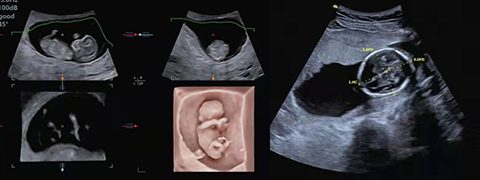

二维早孕筛查 :超高分辨率下呈现羊膜连续完整,颈项透明层清晰可见,满足早期胎儿筛查的临床需求。

输卵管容积造影,二维早孕筛查

孕中实时跟踪

运用3D4D成像技术,实现全方位多角度观察胎儿;自动测量胎儿预项透明层、胎儿双顶径、腹围等,提供胎心ZScore评分表,实时监测胎儿生长情况 。